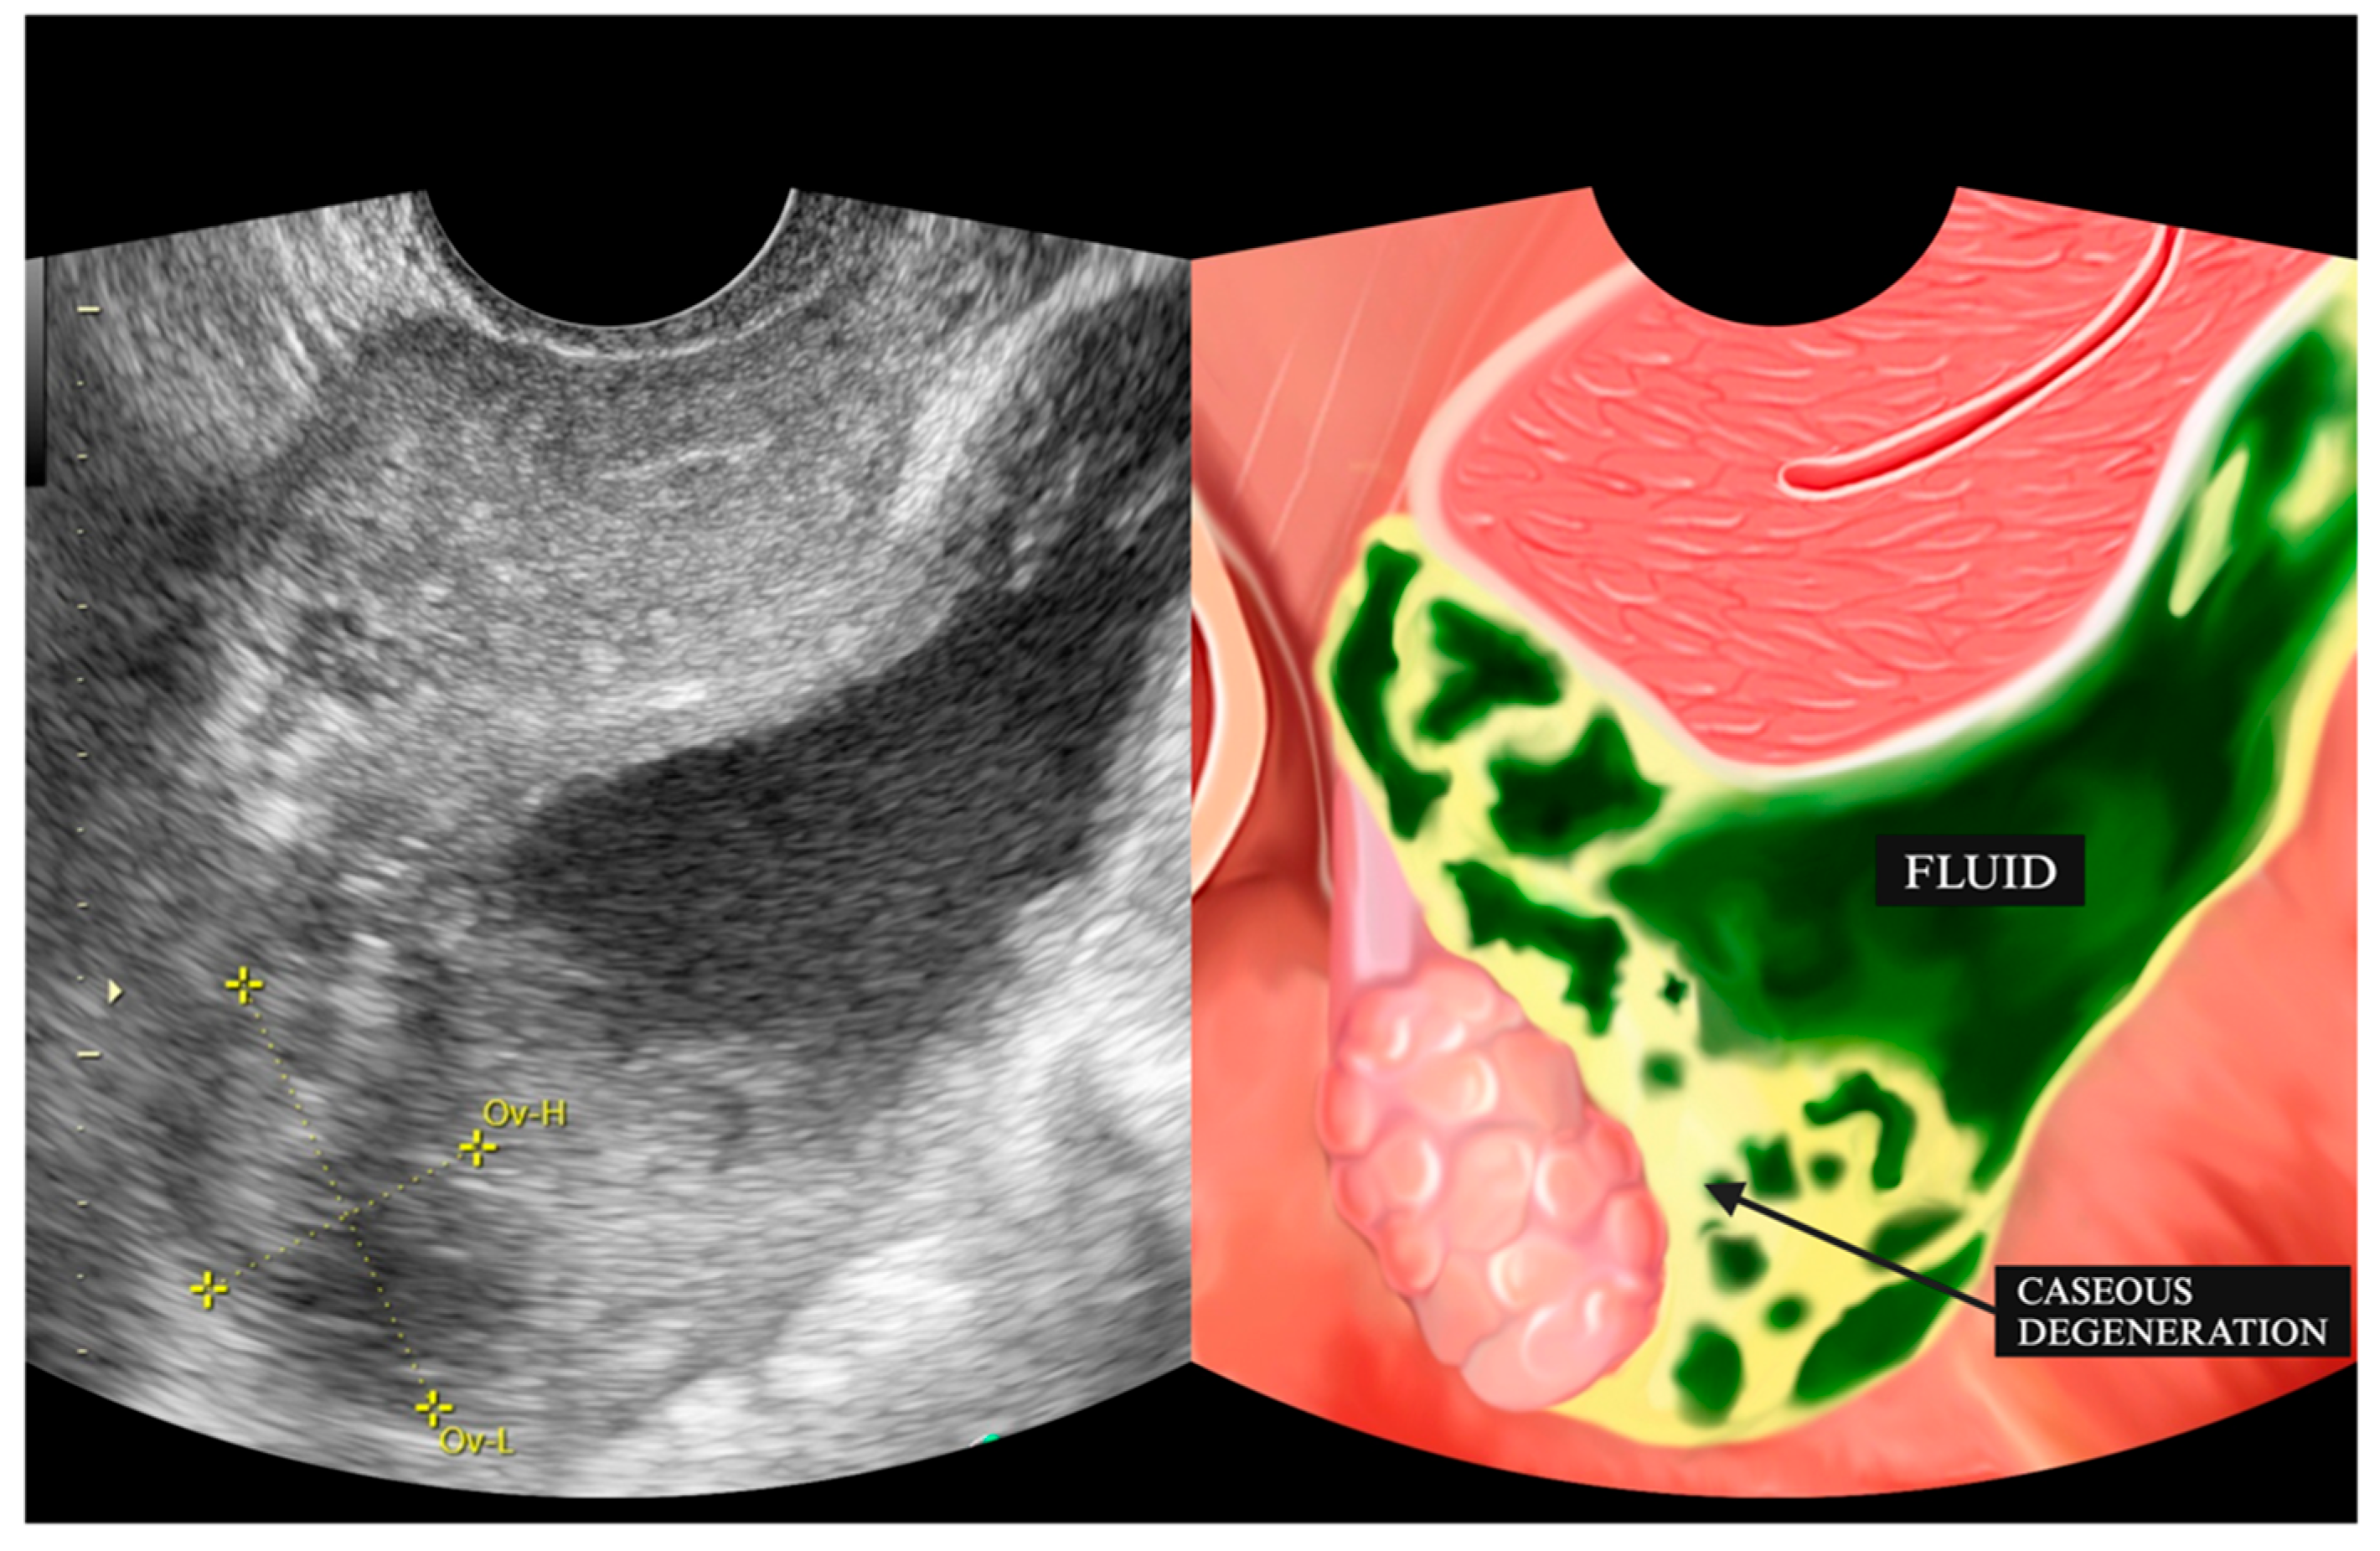

| 3 | IO (31) * | Caseous degeneration on the surface | Adhesion complex | Normal | Adhesion complex | Normal | (−) | Caseous degeneration on the surface of rectosigmoid colon and small bowel |

| 4 | SMK (29) * | Caseous degeneration on the surface. Complex fluid behind uterus | Normal | Not visualized | Adhesion complex with left fallopian tube | Hydrosalpinx | Complex fluid in cavum of Douglas with caseous degeneration | Caseous degeneration on the surface of rectosigmoid colon |